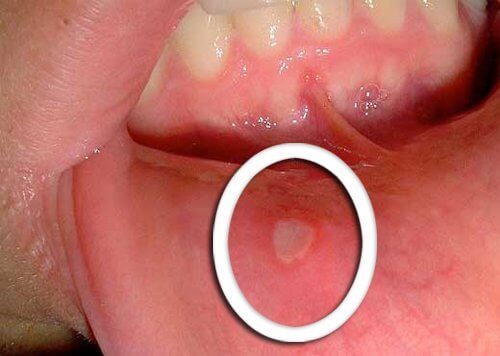

Fysiska förändringar i munnen

- De tidigaste symptomen på orofaryngeal cancer är små sår som inte läker.

- De är vanligtvis röda eller vita och dyker upp på tungan, tandköttet eller läpparna.

- Var uppmärksam på ovanliga förändringar som inte förbättras på några dagar och tala med din läkare.